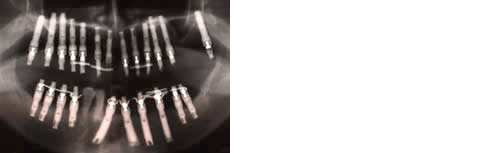

術後13週時のパノラマX線写真では予定した骨高径が得られており、移植骨と母床骨との境界は不明瞭でした(図8)。術後24週時のX線所見では予定した骨高径が得られており(図9)、翌週に同部にインプラントを4本埋入、造成した骨には豊富な血流が認められ、骨質は比較的硬く初期固定は十分に得られました(図10)。インプラント埋入後3ヶ月時にはオステオインテグレーションの獲得を確認し、現在プロビジョナルレストレーションにて機能負荷を開始しているが経過は良好です(図11)。

長期間かけて吸収しかつ高度に皮質化した下顎遊離端欠損部におけるvertical ridge augmentationは難易度の高いケースと考えられます。このような症例に骨形成の促進が期待される超音波治療器を応用した結果、予定した骨高径の獲得および、臨床的に良質な骨の再生が認められ、インプラントによる機能回復が可能となりました(図12)。一般的に、vertical ridge augmentationは骨質、部位、個体差等の条件にも左右されますが臨床上約4mmが限界と報告されています。その理由の一つとして、移植骨部の周囲および内部における新生毛細血管の再生と同部の血流の再開が早期に行なわれ、それらに伴って移植骨部は一時的な吸収機転を経ますが、その体積を減ずる前の早期に骨リモデリングを開始する必要性がある為、量的限界が生じると考えられます。したがって今回のケースではmini screwによる高径の維持に加え、超音波刺激により局所における血流量の増加と細胞に対する適度な刺激により代謝活性の促進が行なわれ、5〜7mmの骨高径を獲得し良好な結果が得られたと推測いたします(図13)。

図11:プロビジョナル レストレーション装置

荷重開始時(二次手術後5日)

図12:術前

図13

図14:垂直的骨高径の獲得量